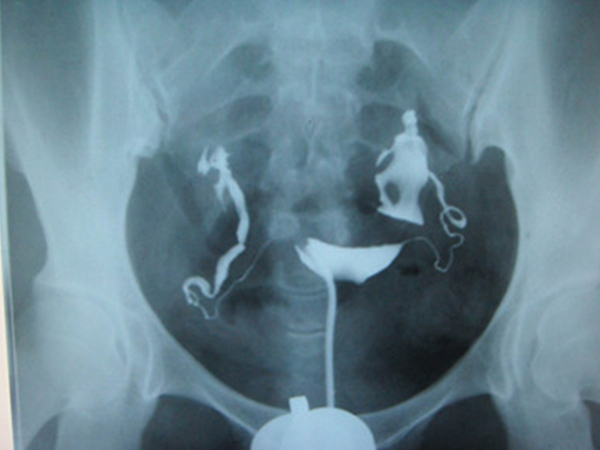

输卵管造影是女性检查输卵管是否通常的主要的方法,该检查能够清晰的显示出宫腔形态以及双侧输卵管的畅通度等。女性做输卵管造影主要有五个步骤,首先确定输卵管造影的时间..